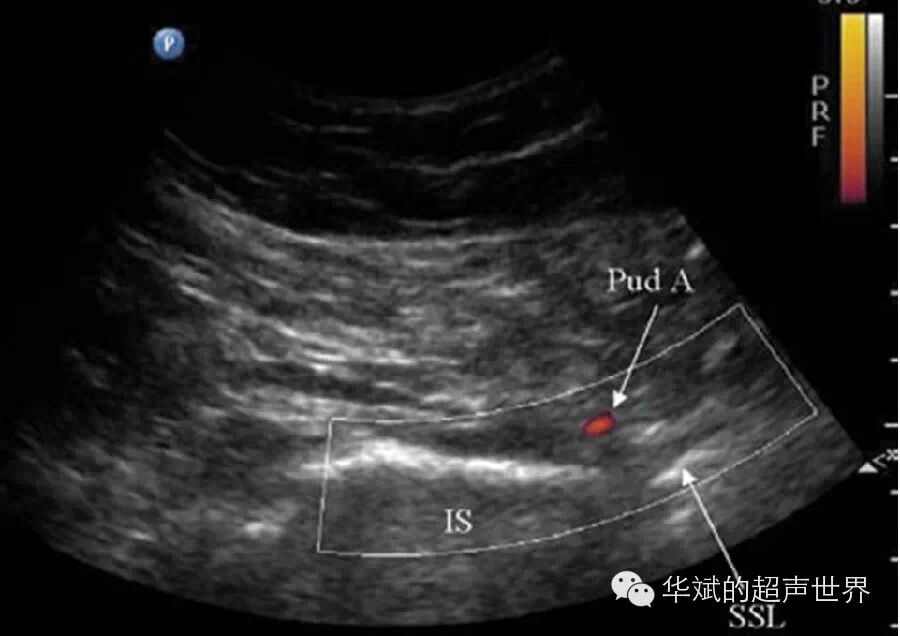

此外还有一种情况,这类神经比较细小、位置深在,二维超声直接显示非常困难,但这些神经有明显的血管伴行,利用彩色多普勒寻找这些血管便成为定位神经为的关键。例如:阴部神经和伴行的阴部动脉由梨状肌下孔穿出并绕行坐骨棘行至会阴部,扫查时于臀部寻找坐骨棘再利用彩色多普勒寻找阴部动脉即可定位阴部神经(图4)。

4 阴部神经定位。Pud A:阴部动脉,IS:坐骨棘,SSL:骶棘韧带